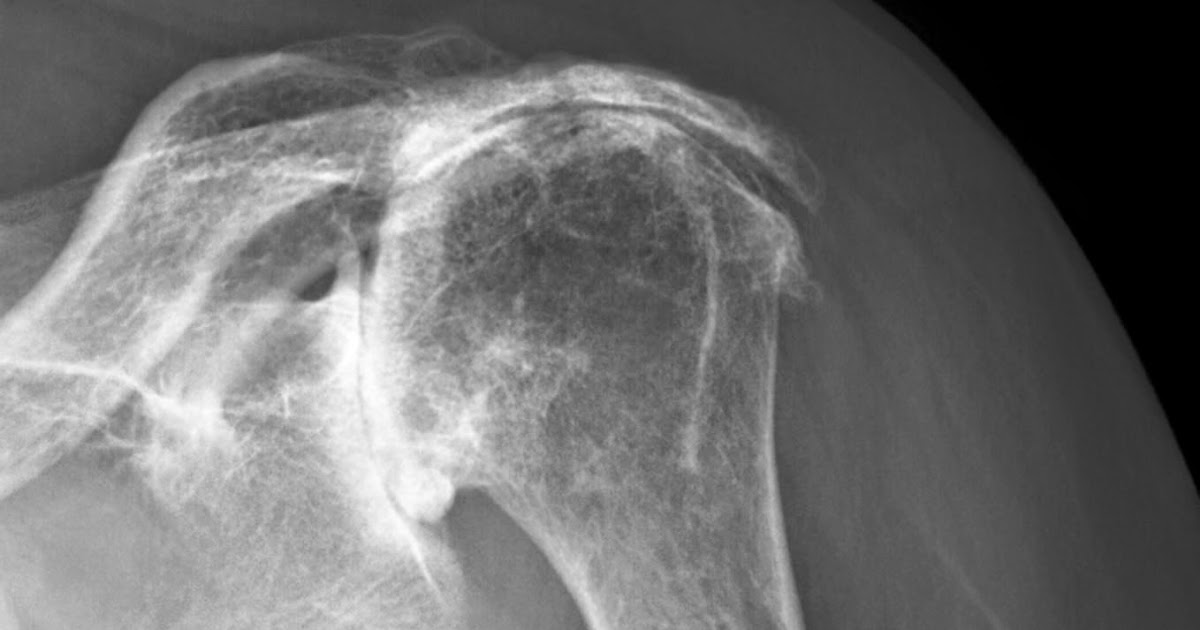

Shoulder Pain Arthritis Or Rotator Cuff . In the shoulder, arthritis causes pain and stiffness that can make it difficult to lift your arm, brush your hair, reach up to a high shelf, or perform. Rotator cuff tear arthropathy is a type of shoulder arthritis that can develop after a massive and prolonged rotator cuff tear. Pain from a problem with the rotator cuff is often called shoulder. The four rotator cuff tendons in your shoulder wrap around the ball portion of the shoulder joint, holding it in The rotator cuff is a group of muscles and tendons that surround the shoulder joint, keeping the head of the upper arm bone. The rotator cuff is a group of muscles and tendons that keep the upper arm bone held in the shoulder blade socket. If you experience shoulder pain at night that makes it difficult to fall asleep or jolts you awake, you may have a tear in one or more of your rotator cuff tendons. Injuries to the rotator cuff are common and can lead to a form of shoulder arthritis called rotator cuff tear arthropathy. The most important facts about cuff tear arthropathy (shoulder arthritis with a. Summary of rotator cuff tear arthropathy.

In the shoulder, arthritis causes pain and stiffness that can make it difficult to lift your arm, brush your hair, reach up to a high shelf, or perform. The most important facts about cuff tear arthropathy (shoulder arthritis with a. The four rotator cuff tendons in your shoulder wrap around the ball portion of the shoulder joint, holding it in Pain from a problem with the rotator cuff is often called shoulder. If you experience shoulder pain at night that makes it difficult to fall asleep or jolts you awake, you may have a tear in one or more of your rotator cuff tendons. The rotator cuff is a group of muscles and tendons that keep the upper arm bone held in the shoulder blade socket. Rotator cuff tear arthropathy is a type of shoulder arthritis that can develop after a massive and prolonged rotator cuff tear. Injuries to the rotator cuff are common and can lead to a form of shoulder arthritis called rotator cuff tear arthropathy. Summary of rotator cuff tear arthropathy. The rotator cuff is a group of muscles and tendons that surround the shoulder joint, keeping the head of the upper arm bone.

Shoulder Pain Arthritis Or Rotator Cuff Summary of rotator cuff tear arthropathy. Pain from a problem with the rotator cuff is often called shoulder. Injuries to the rotator cuff are common and can lead to a form of shoulder arthritis called rotator cuff tear arthropathy. If you experience shoulder pain at night that makes it difficult to fall asleep or jolts you awake, you may have a tear in one or more of your rotator cuff tendons. The four rotator cuff tendons in your shoulder wrap around the ball portion of the shoulder joint, holding it in The rotator cuff is a group of muscles and tendons that keep the upper arm bone held in the shoulder blade socket. Rotator cuff tear arthropathy is a type of shoulder arthritis that can develop after a massive and prolonged rotator cuff tear. The most important facts about cuff tear arthropathy (shoulder arthritis with a. The rotator cuff is a group of muscles and tendons that surround the shoulder joint, keeping the head of the upper arm bone. In the shoulder, arthritis causes pain and stiffness that can make it difficult to lift your arm, brush your hair, reach up to a high shelf, or perform. Summary of rotator cuff tear arthropathy.